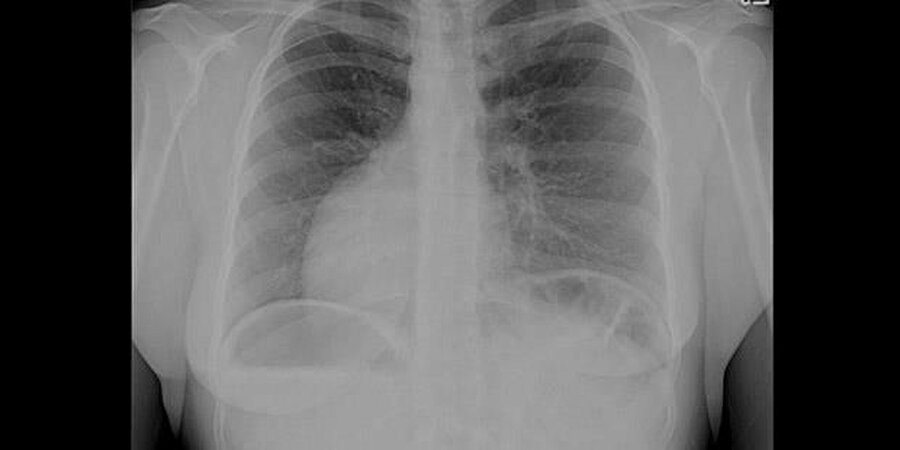

Uzun süredir mide ağrıları yaşayan ve ardı ardına hastanelere gitmesine rağmen net bir tanı konamayan Aslan, son olarak Gaziantep Şehir Hastanesi’ne başvurdu. Burada yapılan detaylı incelemelerde Aslan’ın kalbinin sağda, midesinin ve dalağının yine sağ tarafta; karaciğer ve safra kesesinin ise solda olduğu tespit edildi.

Bu sıra dışı anatomik duruma tıpta “situs inversus totalis” adı veriliyor.

“Hasta karın ağrısı şikâyetiyle geldi. MR görüntülemede tüm organların tam tersi şekilde yerleştiğini gördük. Aynı zamanda safra kanalında taş vardı ve tekrarlayan pankreatit atakları geçiriyordu. RCP işleminde hastayı ters pozisyonda almak zorunda kaldık. Oldukça zorlu bir işlem olmasına rağmen başarılı bir şekilde tamamladık” dedi.